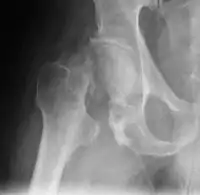

ακτινογραφία εξάρθρωσης λεκάνης

- (ιατρική): η μετακίνηση οστού εκτός άρθρωσης, το βγάλσιμο της κεφαλής ενός οστού από την κοιλότητα στην οποία βρίσκεται συνήθως